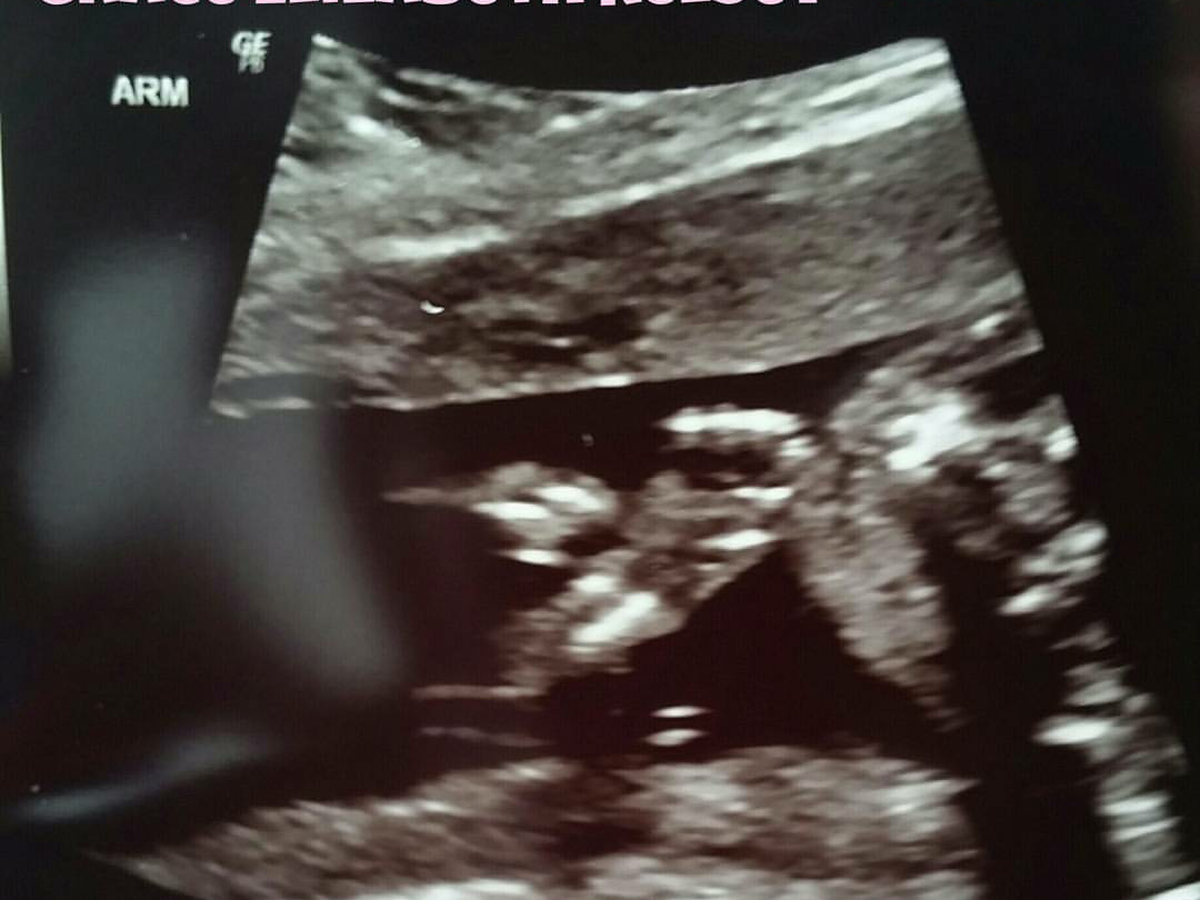

Two months ago we had an ultrasound of our second child (Grace Elizabeth Kelsey). After the doctors reviewed the images, they called to tell us that she had a minor heart defect (a hole in her heart) and that it was quite common. They scheduled us for a second ultrasound to be sure of their diagnosis.

On the second ultrasound they determined it was not as common as they thought, that Grace had a condition called TGA (Transposition of the Greater Arteries). This is a rare condition where the vessels are swapped. One out of every 20,000 babies have this. This condition would normally require an open heart surgery at birth and after that Grace should be ok. This prompted the doctors to send us for an echo cardiogram to get a better look at her heart.

This time they determined that not only does Grace have TGA but she also has a right ventricle that does not function and will never function. She will now need 3 open heart surgeries. One when she is born, one at 4-6 months and one at 2 years old.